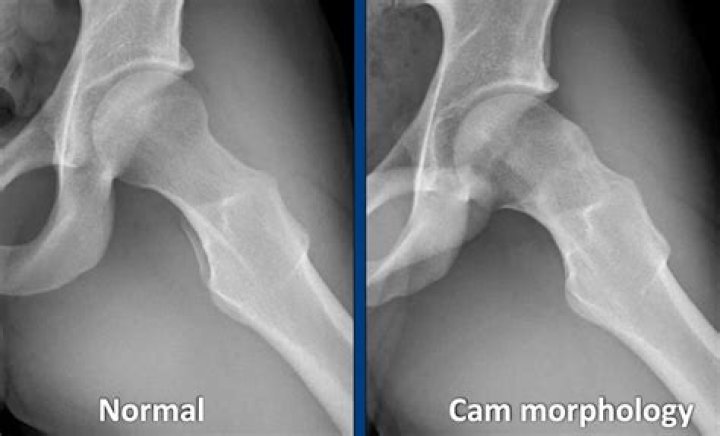

What is a cam deformity of the hip?

A deformity of the ball at the top of the femur (called cam impingement). If the head is not shaped normally, the abnormal part of the head can jam in the socket when the hip is bent. This may occur during activities such as riding a bicycle or tying your shoes.

Cam deformities are due to loss of the sphericity (round shape) of this femoral head. As a result, the labrum can become “pinched” between the bone of the socket and the bone of the ball and is referred to as femoroacetabular impingement or FAI.

The CAM for (CAM comes from the Dutch word meaning “cog”) describes a shape of the ball (femoral head) that is aspherical or not perfectly round. This loss of roundness of the femoral head contributes to a damaging, abnormal contact between the head and socket.

Cam impingement occurs when the femoral head is not perfectly round and cannot rotate smoothly inside the acetabulum. It often results from a bump formed from excess bone growth at the end of the femur. During movement, the bump grinds the cartilage inside the acetabulum.

Cam morphology refers to an abnormal morphology of the femoral head-neck junction interlinked with an osseous asphericity of the femoral head. It is one possible cause of femoroacetabular impingement (FAI).